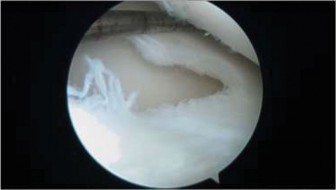

The correct answer is (C). The arthroscopic images demonstrate a complete discoid meniscus which is covering the entire lateral tibial plateau. As the patient is symptomatic from the meniscus, saucerization is the first step in management. The meniscus is trimmed back using a combination of shavers and biters to a stable peripheral rim, which replicates the width of the native meniscus. Complete meniscectomy would not be indicated in a patient of this age due to the high risk of early onset degenerative arthritis. In fact, even prior to intervention, many discoid menisci have been associated with the development of lateral hemijoint osteochondral lesions. Although chondroplasty may be necessary, the meniscus is the underlying problem causing chondral wear and must be dealt with first. After saucerization is performed, the meniscus is probed and the following arthroscopic image is seen (Fig. 10–33). The next step in management is:

Figure 10–33

The correct answer is (D). The arthroscopic image demonstrates an unstable peripheral rim of the meniscus which an attempt should be made to repair. The meniscus has been trimmed adequately but instability remains. Further saucerization without repair may lead to very little to no meniscus remaining which can lead to early degeneration. Although chondral damage may be present in association with the meniscus, there is no exposed subchondral bone to suggest the need for microfracture. Various repair techniques (inside-out, outside-in, all-inside) are available to the surgeon and should be utilized based on surgeon preference and experience. Objectives: Did you learn...?